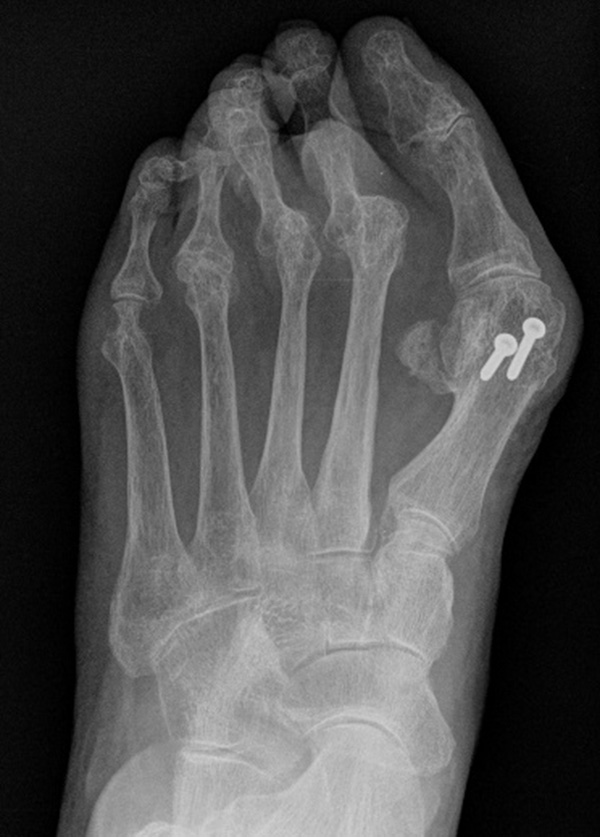

Die Arthrodese des Großzehengrundgelenks in Kombination mit einer Resektionsarthroplastik der Metatarsaleköpfchen der Kleinzehen führt zu guten klinischen Langzeitergebnissen bei Patienten mit rheumatoider Arthritis und destruiertem Metatarsaleköpfchen 34. Auch aktuelle Metaanalysen zeigen, dass dieses Verfahren den Standard bei dieser Pathologie darstellt und dass sich insbesondere auch gelenkerhaltende Therapieverfahren an diesen Ergebnissen messen müssen 35. Triolo et al. 11 berichteten über die Ergebnisse von 89 Füßen (62 Patienten) mit einem Follow up von mindestens 4 Jahren. Der AOFAS Score verbesserte sich nach Arthrodese am Großzehengrundgelenk und OP nach Tillmann Metatarsale II-V von präoperativ 33,4 ±16 auf 82,9 ± 11,9 Punkte. Schlechte Ergebnisse wurden beobachtet bei Patienten mit Revisionseingriffen aufgrund von Pseudarthrosen, verzögerter Knochenheilung, ungenügender Knochenresektion der Metatarsalia und störendem Osteosynthesematerial. Hulse et al. 36 verglichen die Ergebnisse nach Tillmann OP mit und ohne gleichzeitiger Resektion des Metatarsale I Kopfes. 44% der Patienten bei welchen das Großzehengrundgelenk erhalten wurde benötigten im 5-Jahres Follow-up einen weiteren Eingriff an diesem Gelenk. Die Autoren empfahlen daher, das Großzehengrundgelenk in jedem Fall in das Therapiekonzept einzubeziehen. Eine Langzeit Kohortenstudie an 203 Patienten (370 Füße) mit einem Follow-up von 11,4 Jahren wurde von Jüsten et al. veröffentlicht 10. 90,2% der Patienten berichteten über eine signifikante Besserung der Beschwerden, 87,5% über eine Besserung der Gehstrecke.

Thomas et al. 37 führten eine prospektive Kohortenstudie an 23 Patienten (37 Füßen) durch. Durchgeführt wurde die Resektion aller Metatarsaleköpfchen über drei dorsale Inzisionen. Nach 64,9 Monaten lag der AOFAS Score bei 64,5 Punkten, der durchschnittliche Hallux valgus Winkel lag bei 22,3°. Es kam zu keinen Revisionseingriffen.